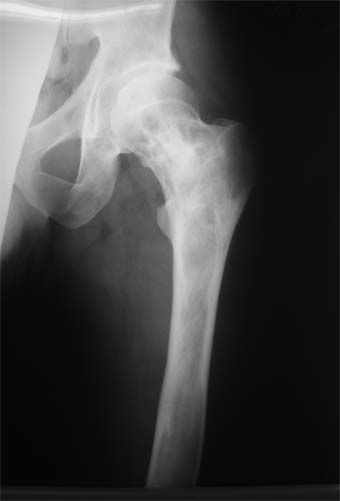

Коллеги!Пациент Д., 35 лет, В 1985 году был поставлен диагноз гемигипоплазия правой нижней конечности. Укорочение 5 см, в 1987 году остеотомия правого бедра, аппарат 4 месяца, удлинили на 2 см из-за нагноения спиц аппарат сняли.

Эти жалобы беспокоят втечение 5-6 лет. В 1999 году выявили "изменения" (со слов больного, выписки нет на руках) бедренной кости и костей голени слева. Тогда же предложили в ЦИТО срочно делать какую-то операцию.

Левая нижняя конечность. Левое бедро увеличено в объеме, при пальпации пальпируется бедренная кость большего диаметра по сравнению с левым бедром. Пальпация безболезненна.

В приложении вид больного и рентгенограммы бедра 2001 год и 2005 год.

2001

2005

Что бы это могло быть? О чем можно думать? Онкология?

Похоже на болезнь Педжета.

Остеосклеротическая стадия болезни Педжета. Имею двух подобных больных по 15 -20 лет наблюдения. В острой стадии - текли как классическая саркома. "За" - все (рентген+биопсия+клиника) - отправили хоронить, а в результате живы и имеют рентген-картинку похожую Вашей. Поройтесь в минеральном обмене и в почках. Удлинять подобные кости опасно. Можно -биопсию на всякий случай (из зоны склероза и зоны пороза).

У больного полиоссальноая форма фиброзной дисплазии с поражение левой бедренной и большеберцовой кости. На рентгенограммах - тотальное разрастание и остончение кортикального слоя. Имеется удлинение левой нижней конечности на 2,5-3 см за счет голени. Больному показано оперативное лечение левой большеберцовой кости.